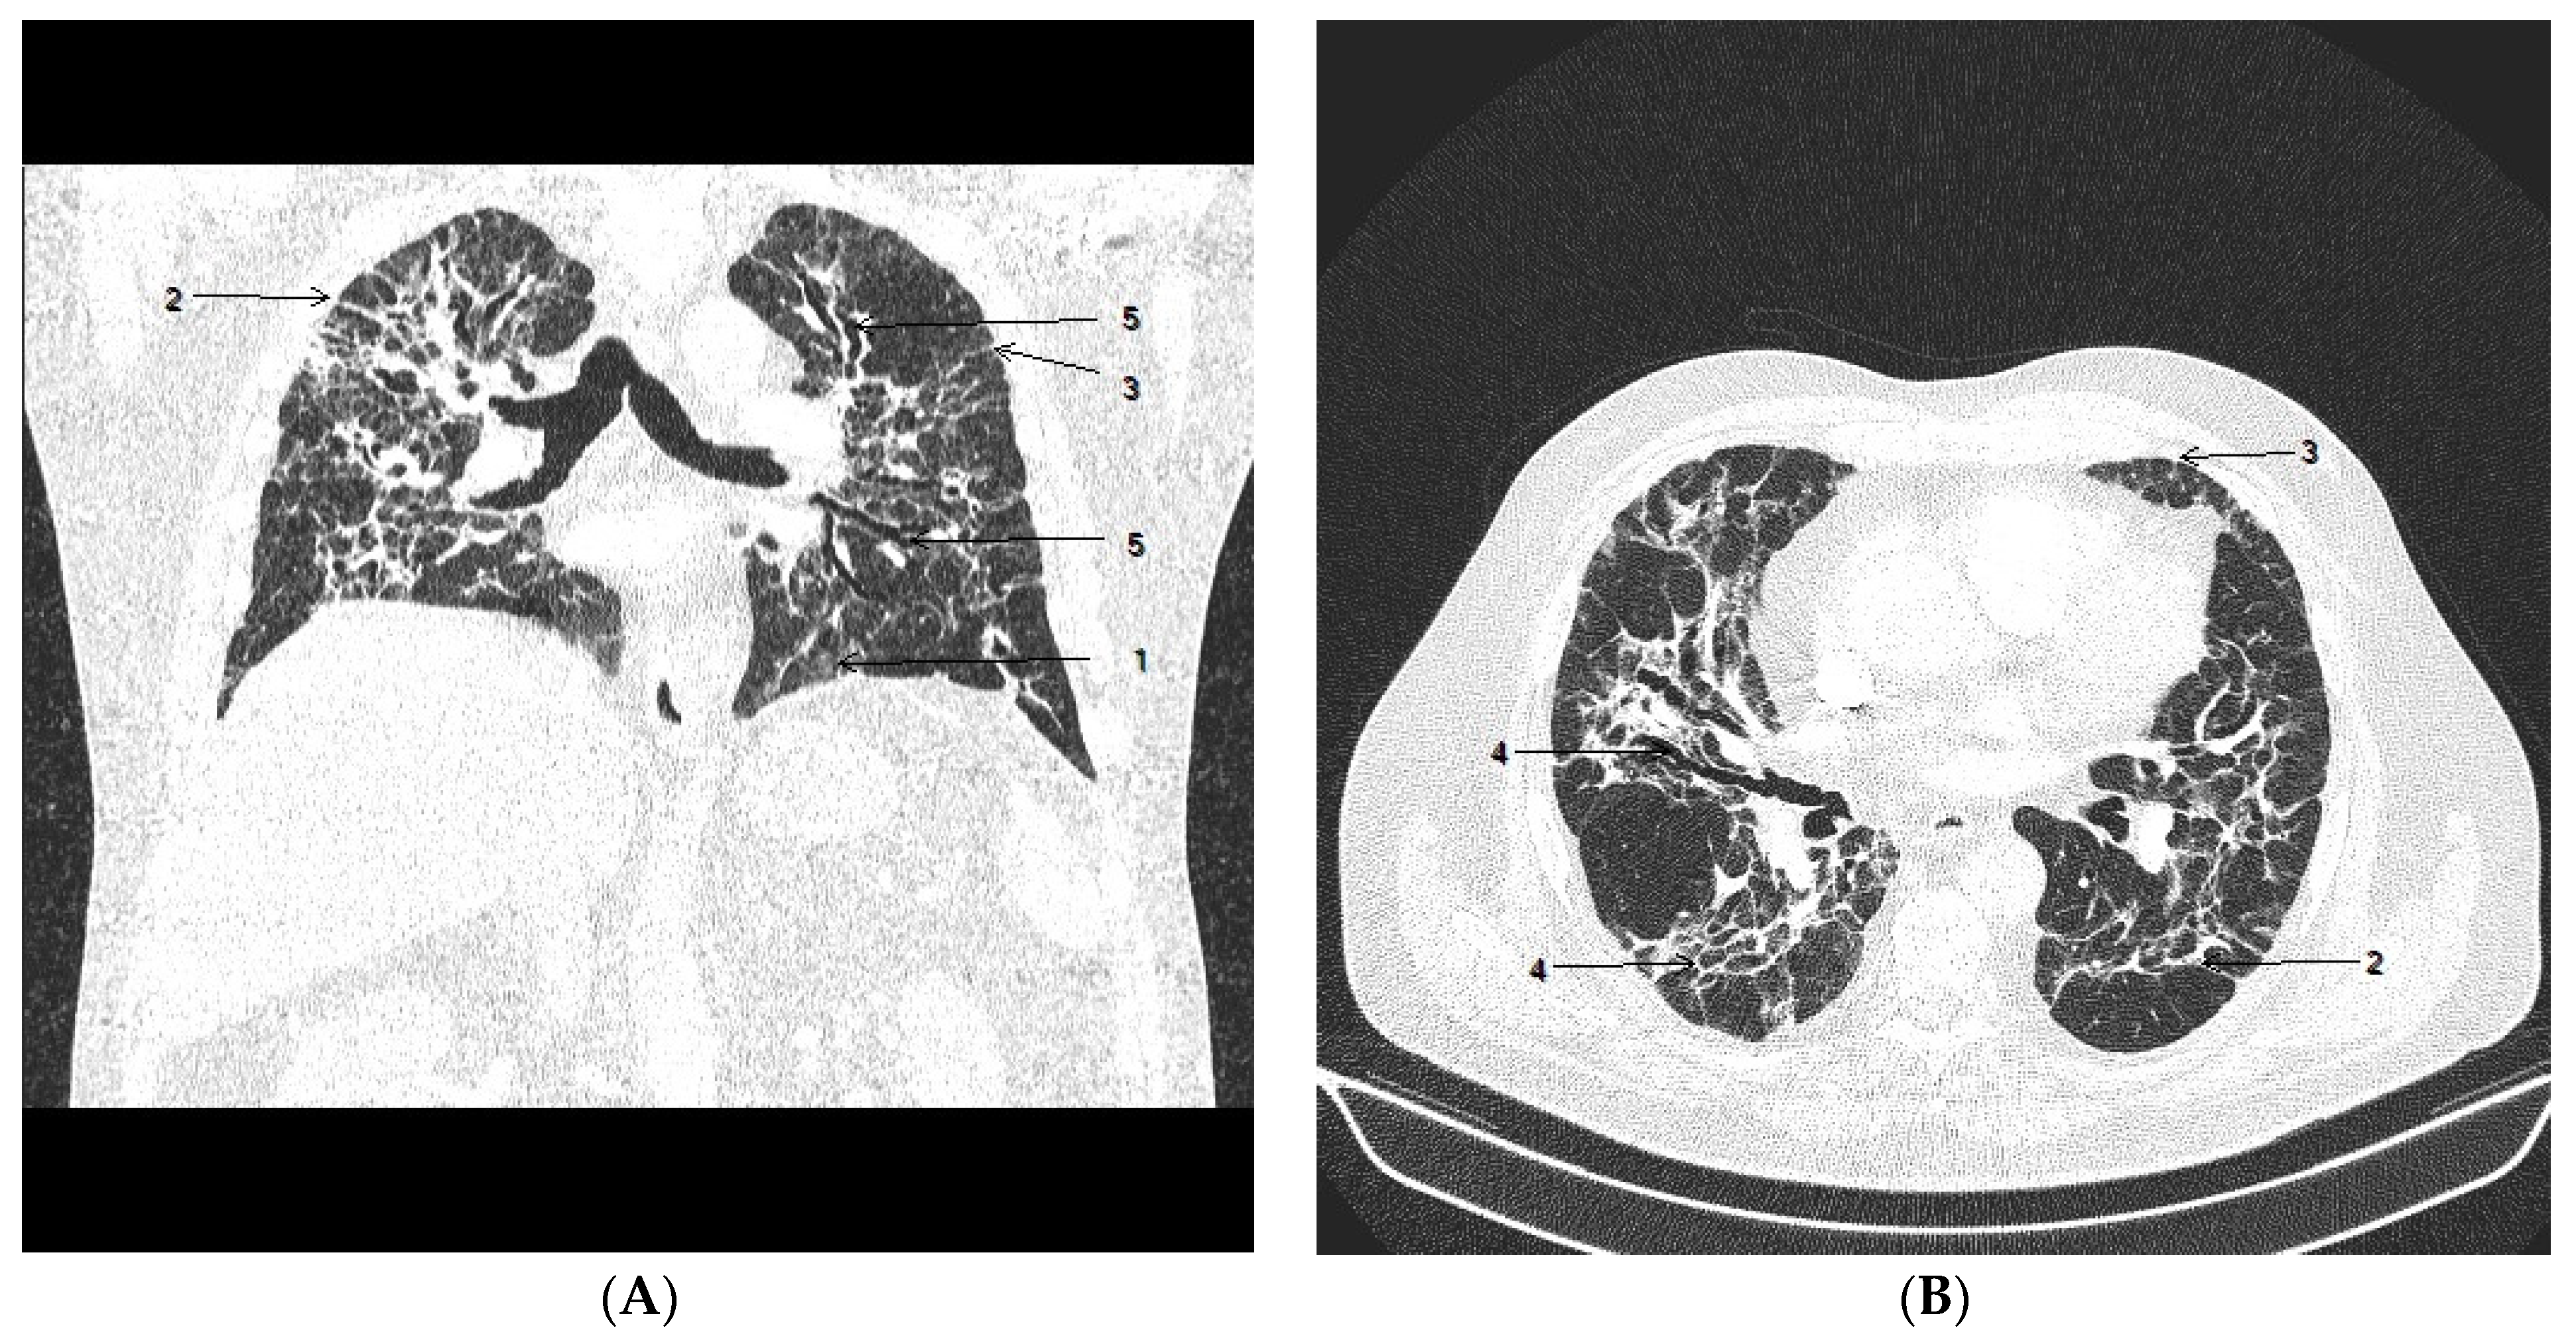

2. Case Presentation

2.1. Clinical Course

2.2. Autopsy Investigation